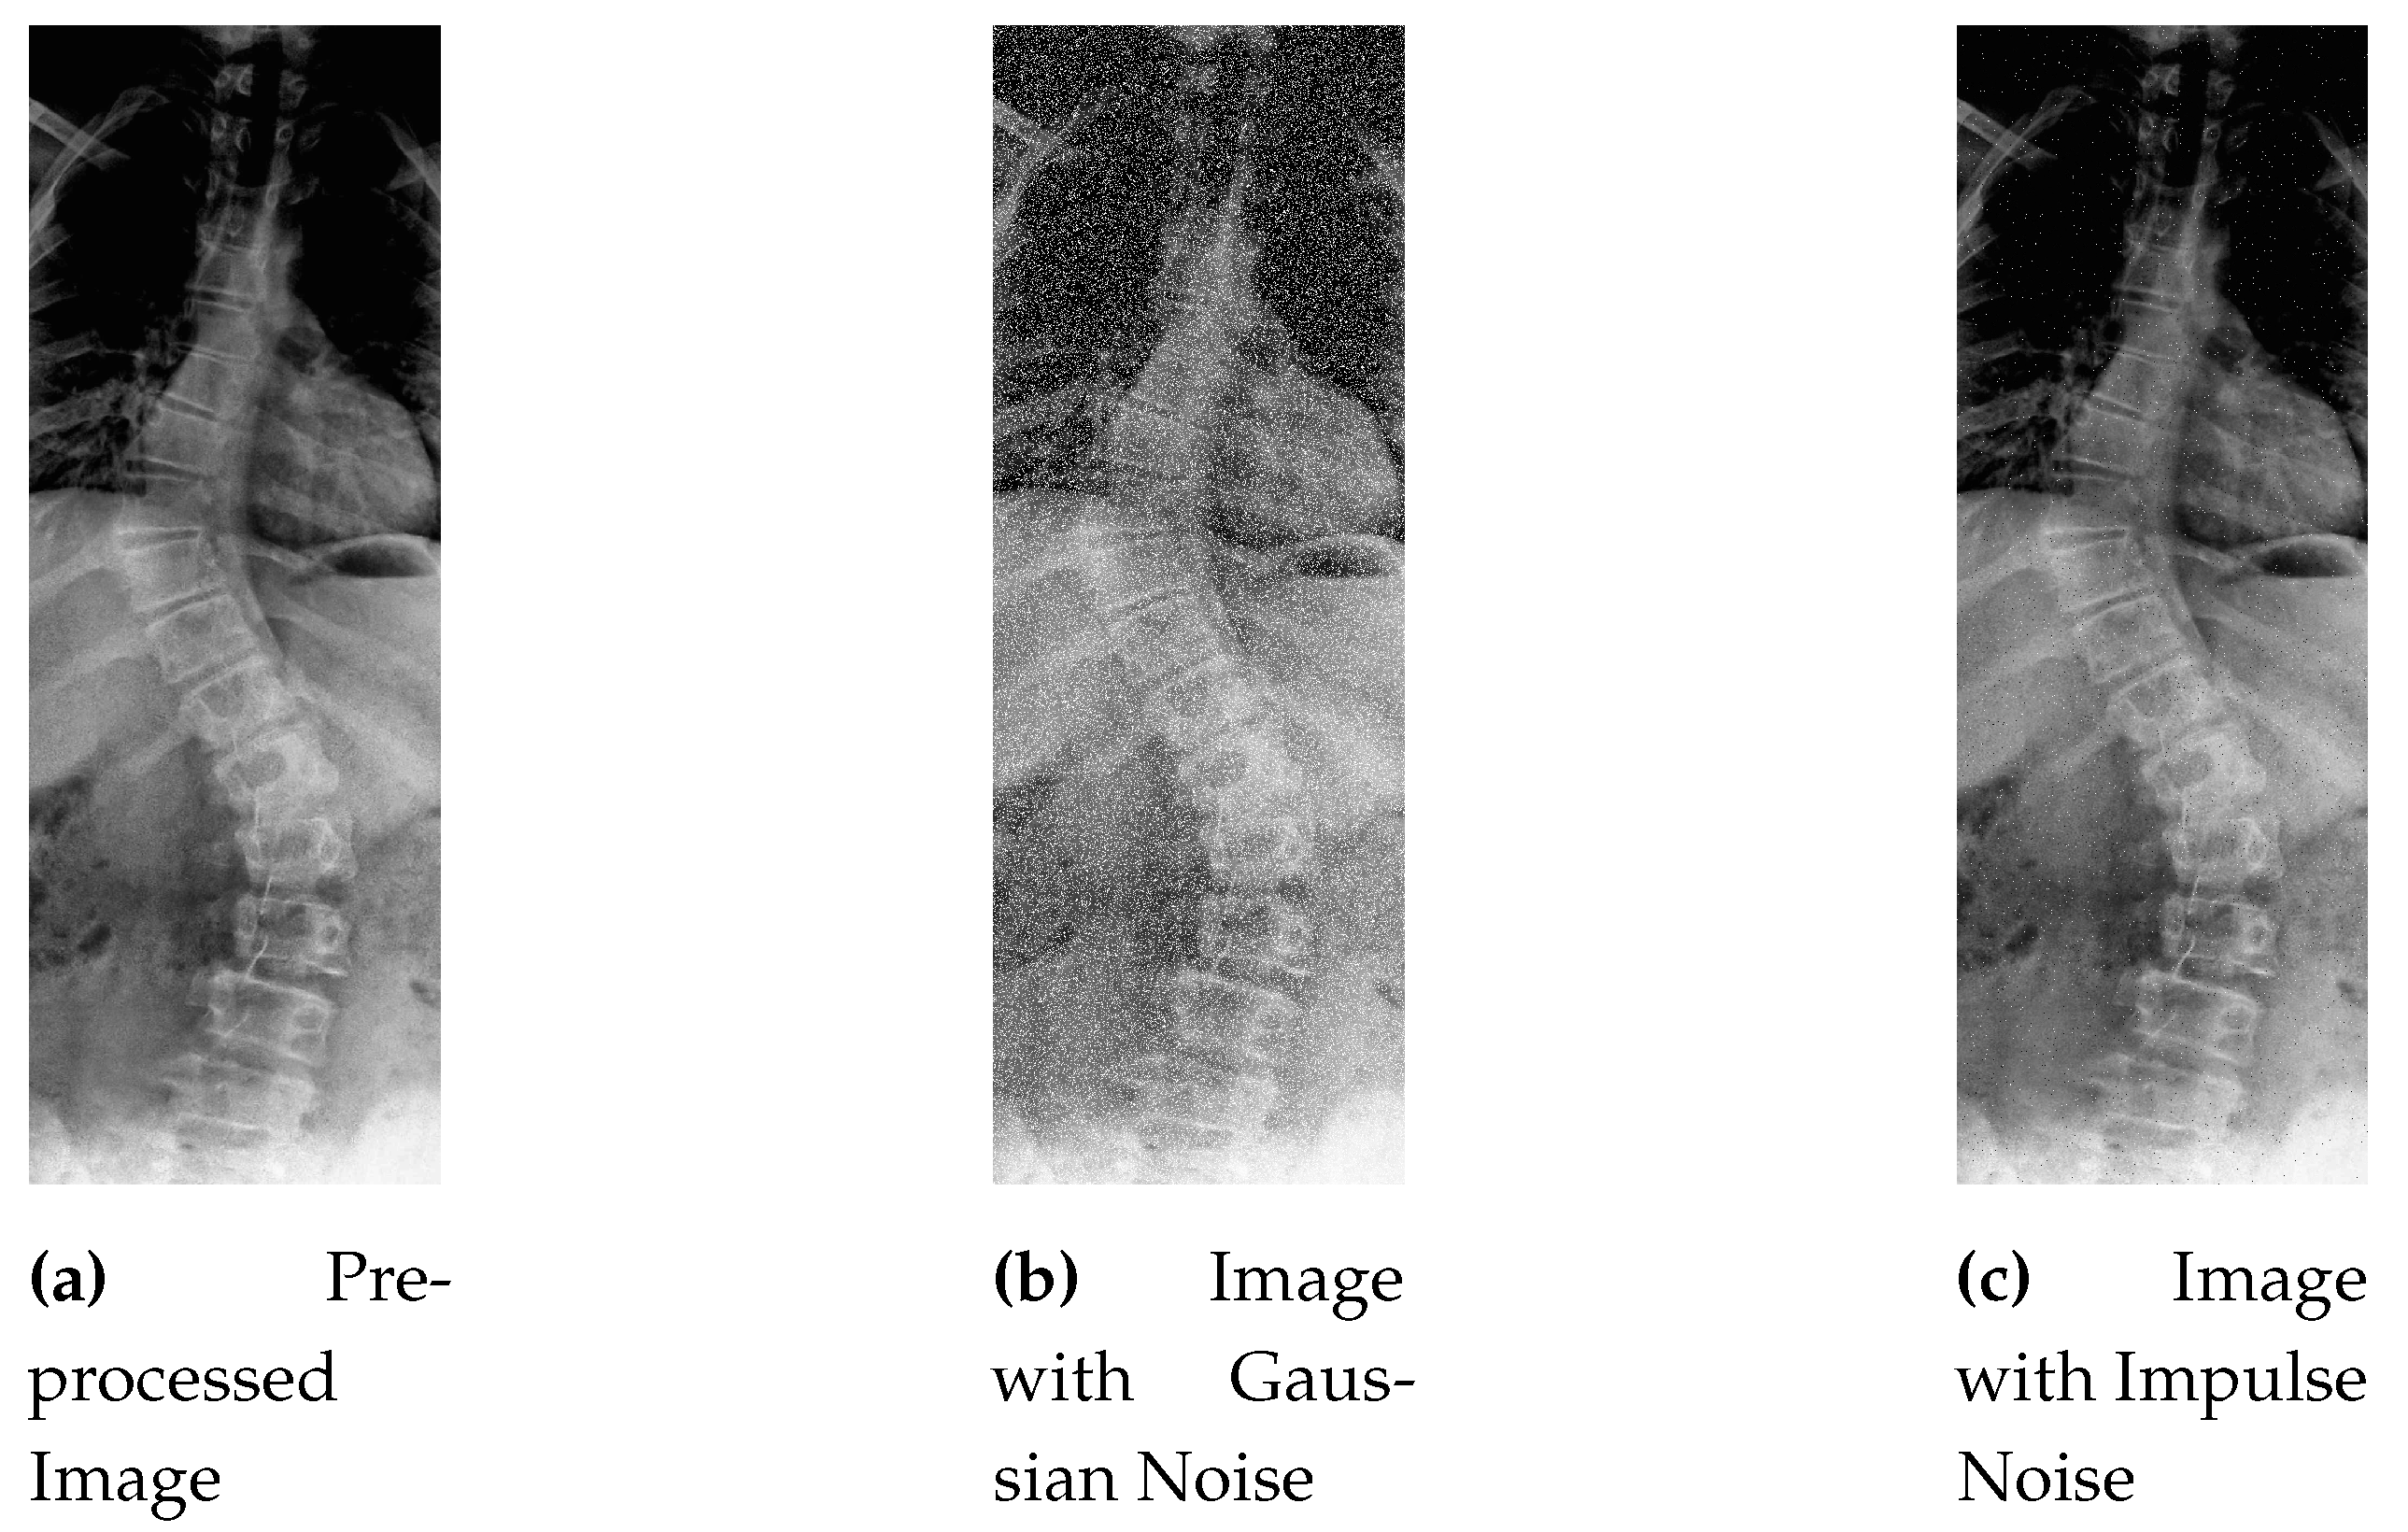

In general, X-ray images contains Salt-and-Pepper and Gaussian noise due to various reasons like poor tissue contrast, patient posture, unexpected movement, sensor limitations and machine tolerance [48]. In this work, a selected ratio of these noises are added to the pre-processed dataset.

Figure 6 shows the grainy and speckled effect of Gaussian noise to the sample image.

This process introduces random variations to the pixel values, creating the characteristic salt-and-pepper noise pattern in the image as shown in Figure 7.

After contrast improvement, Gaussian noise is added in 10 % of total dataset (481 samples), and in the next 10 percent, Salt-and-Pepper noise is added. Gaussian and Impulse noise additive image in comparison to the pre-processed image can be seen in Figure 15.

Figure 6. Image with Gaussian Noise.

Figure 7. Image with Salt-and-Pepper Noise.

Figure 15. Pre-processed Image with Gaussian and Impulse Noise.